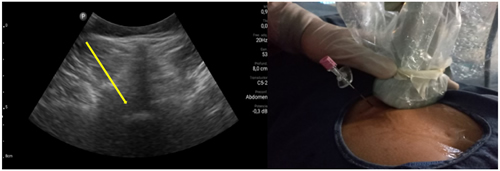

Pacientes y métodos: Un total de 25 pacientes con dolor radicular lumbosacro fueron seleccionados para recibir inyecciones epidurales interlaminares de esteroides en posición decúbito dorsal, utilizando la técnica ecoguiada en plano, en tiempo real, en eje corto o transversal. En todos los casos, un epidurograma de control fue realizado previo a la inyección de la solución de esteroides. El rendimiento de la técnica fue estudiado mediante la tasa de éxito de la misma, entendido como éxito a la obtención de un epidurograma sin necesidad de abandonar la técnica ecográfica en un tiempo menor a 10 minutos. El rendimiento del procedimiento fue estadísticamente evaluado por el método de la suma acumulativa (CUSUM), y la curva de aprendizaje aplicando este método fue construida.

Figura 1

Figura 2